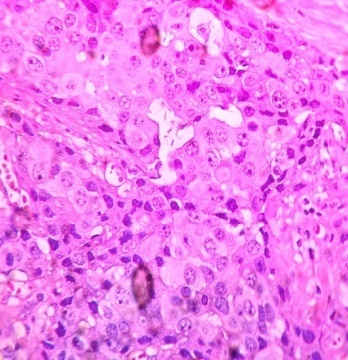

Then, the patient was subjected to modified radical mastectomy with axillary clearance, and a diagnosis of invasive duct carcinoma of the breast, no special type, with pT4N2aMx (fig. 4) was made.

Fig. 4: H and E microphotograph showing invasive duct carcinoma cells in 40x